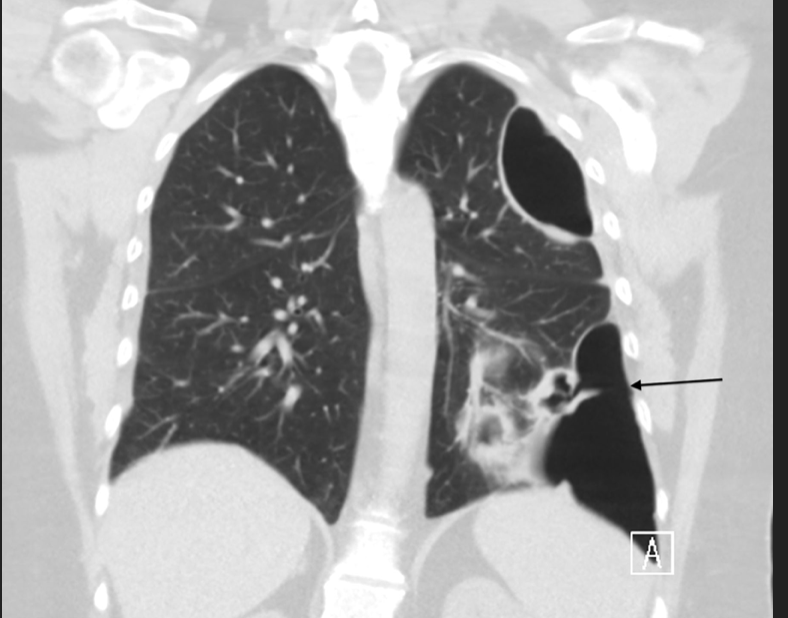

What are findings of a pneumothorax on a CXR?

CXR

ABG: determine severity of pneumothorax/ resp distress